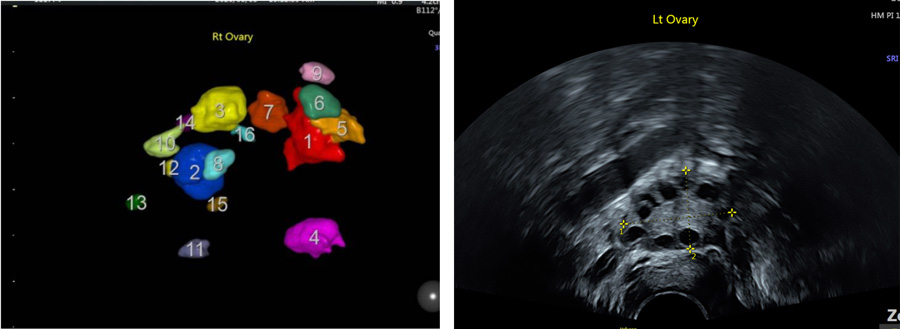

在檢測技術上,茂盛醫院獨有的精蟲穿透力分析,可以準確判斷出精卵的結合能力;亞洲少見的4d超音波,有別於傳統的黑白2D超音波,可以清楚的看出卵子個數以及子宮形狀,做為醫師選用療程、用藥、及植入上的參考。

(左邊的彩色4D超音波較黑白的2D超音波更能精確判斷,每個顏色就是一顆卵子)